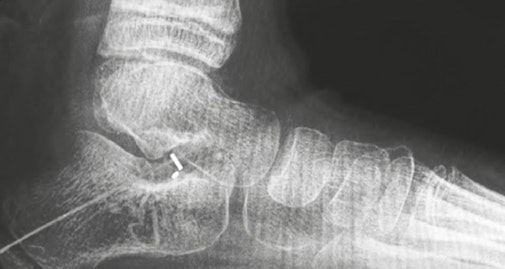

Figure 1 Vector™ Hammertoe Correction System depicts a postoperative radiograph of three hammertoe fusions with the PEEK-OPTIMA HA Enhanced PIPJ fusion devices and one fusion with a K-wire for comparison

Figure 2 PIPJ arthrodesis of 2nd, 3rd, and 4th ray using the Vector™ Hammertoe Correction System manufactured from PEEK-OPTIMA™ HA Enhanced (right). The visible metallic component is a patented tantalum structural encoded identifier for Unique Device Identification (UDI). Images provided courtesy of Nvision Biomedical Technologies. ©Nvision Biomedical Technologies.